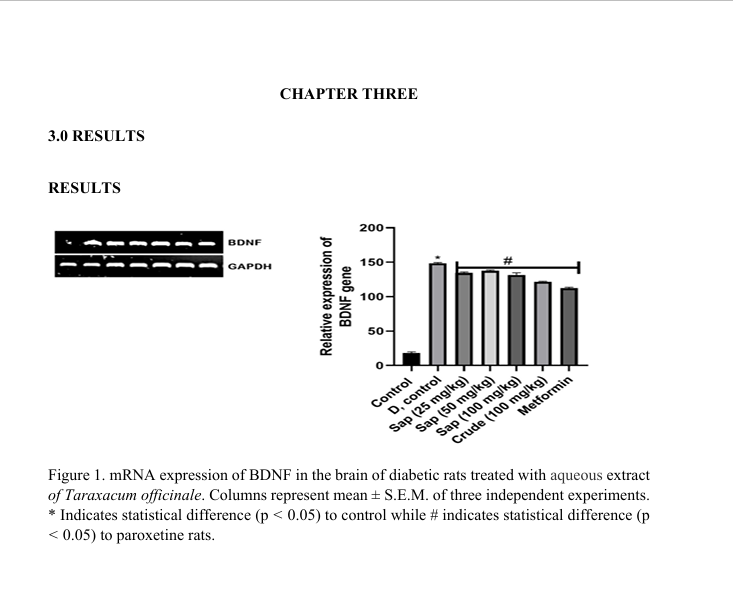

Molecular Effect of Taraxacum Officinale on Marker Gene in the Brain of Streptozotocin Induced Diabetic Rat